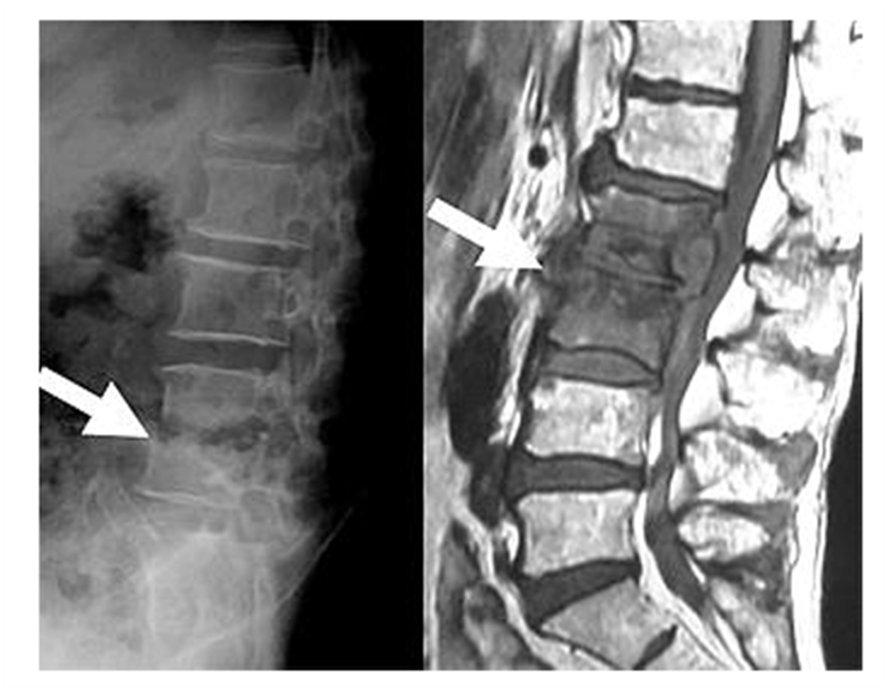

82歳の女性で腰痛と体重減少、CRP高値、白血球増多で外来に紹介受診された。お年寄りの感染症で定番は「肺炎」、「尿路感染」、「胆嚢炎」だ。まず外来で胸の写真、尿検査を行ったけれどなんともない。感染源がわからないので、胆石があるのかもしれないと思い、胸腹部CTを撮ってみた。するとなんと胆のうは何ともないが、腰椎に化膿性脊椎炎が見つかった。第1、第2腰椎の周囲に膿瘍の疑いがあるという。

腰痛と炎症反応は脊椎炎が、その原因だった。高齢者の脊椎炎は話には聞いたことはあるが、お目にかかるのは初めてだ。高齢者がかかりやすい「感染症リスト」に脊椎炎も入れておくべきだろう。でも一体、どこから感染したのだろう?